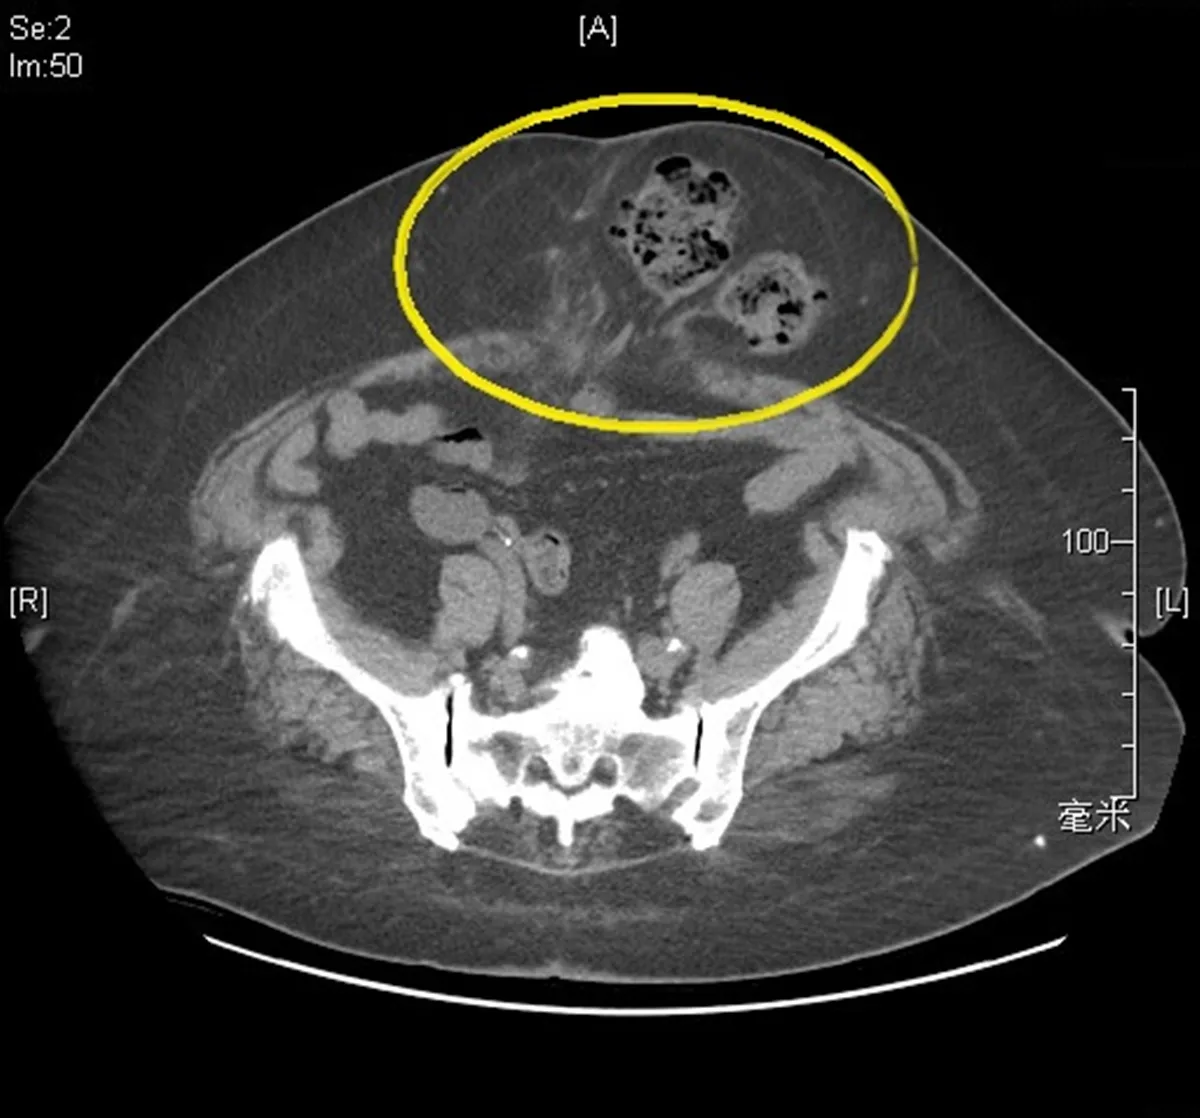

腫瘤手術的地方鼓鼓的,難道是癌症復發?76歲的程先生多年前因腹腔腫瘤接受傳統開腹手術,術後追蹤狀況一直很穩定。近期他發現手術疤痕上方逐漸隆起,尤其在咳嗽或搬重物時腫塊特別明顯,平躺時卻又消失,他擔心是腫瘤復發,急忙就醫檢查。醫師精確檢查確定非癌症復發,而是腹部手術常見的併發症腹壁切口疝氣。

土城長庚醫院一般外科主任黃崧峰指出,腹壁切口疝氣是腹部手術後常見的併發症之一。根據統計,曾接受傳統開腹手術的患者中,發生率約佔10%到30%。其主要成因是腹壁的筋膜或肌肉層在術後未能完全癒合,導致腹腔內的腸道或脂肪組織經由這個缺口向外突出,進而形成在皮膚表面可觸及的腫塊。